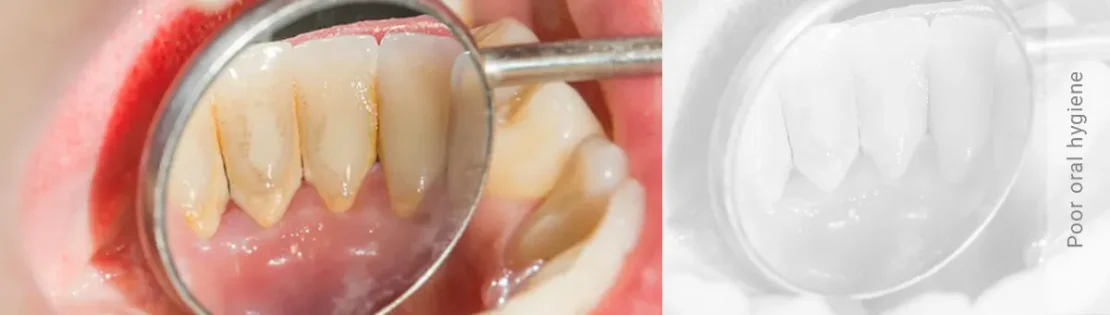

بهداشت ضعیف دهان و دندان

یکی از دلایل اصلی تحلیل رفتن لثه، عدم رعایت بهداشت دهان و دندان است. مسواک زدن غیر اصولی یا ناکافی باعث ایجاد پلاک و جرم در اطراف دندان ها و در مارجین لثه می شود که می تواند لثه ها را تحریک و ملتهب کند و در نهایت منجر به تحلیل آن ها شود.